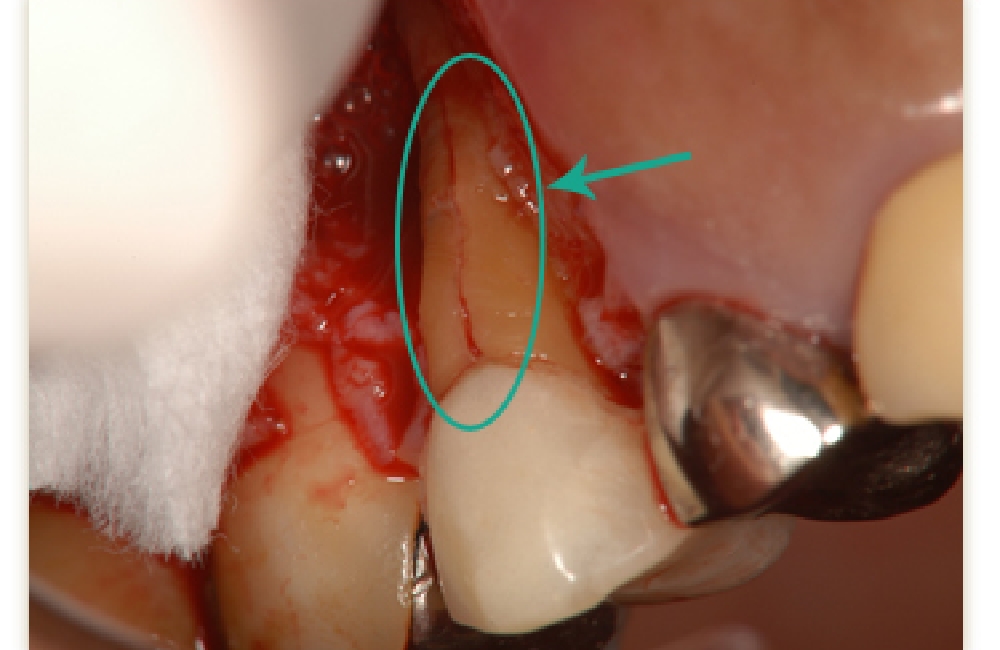

口腔内接着法

破折部分が比較的小さい場合に行う方法です。

破折部を洗浄し、新鮮な歯質を露出させたうえで、生体親和性の高い接着剤を用いて封鎖します。